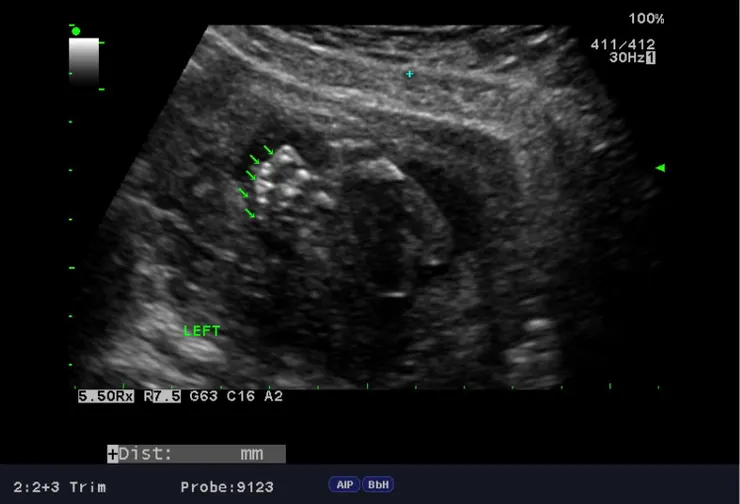

台兒的檢查並不是直接由醫師進行,是由放射師先針對外貌與所有器官進行第一輪初步的掃描,當時放射師照了照肚子裡的寶寶,正要進行著名的「數手指、數腳趾」程序時,寶寶很配合地張開了左手,讓我們數到了五根左手指,但右手卻一直緊握著,遲遲不肯張開,我喝了幾口特別準備的珍珠奶茶,放射師壓壓我的肚子,試圖讓寶寶活動起來,只見睡得香甜的寶寶,一點也不受外界干擾,放射師最後只好放棄,希望下一輪醫師掃描時,寶寶能熱情地張開雙手,完成手腳數數程序。